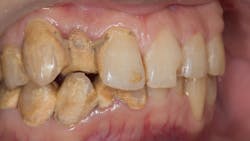

Dental pros may know the prevalence of periodontal disease and how its presence increases the risk of patients developing myriad oral and oral-systemic problems. Among those issues is calculus bridge—a buildup of calculus to an extent that it creates a “bridge” across adjacent teeth. In more severe cases, it can spread into the gumline or up along the surface of the teeth.